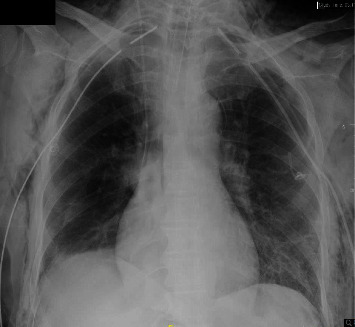

呼吸暂停测试是诊断脑死亡或更具体地说是脑干死亡的标准方法;然而,必须认识到在此过程中可能会造成肺损伤,并遵循可降低并发症风险的临床实践指南建议。有两例气压创伤导致气胸的病例是在使用高于建议氧流量的呼吸暂停测试中发生的。需要更多的数据来明确这种危及生命的并发症的机制和发生率。

Apnea testing is a standard method when diagnosing brain or more specifically brainstem death; however, it is imperative to acknowledge the potential for lung injury during this procedure and follow clinical practice guideline recommendations that may reduce the risk of complications. Two cases of barotrauma leading to pneumothorax occurred during apnea tests that used higher-than-recommended oxygen flow rates. Additional data are necessary to clarify the mechanism and incidence of this life-threatening complication.